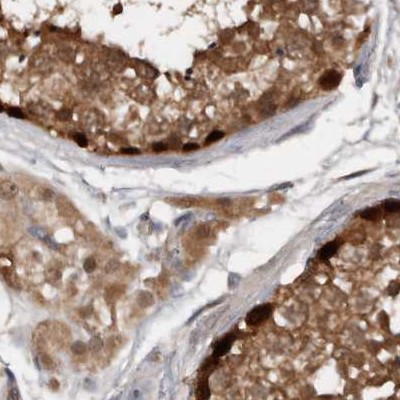

Immunohistochemistry analysis in human adrenal gland and cerebral cortex tissues using Anti-RBKS antibody. Corresponding RBKS RNA-seq data are presented for the same tissues.